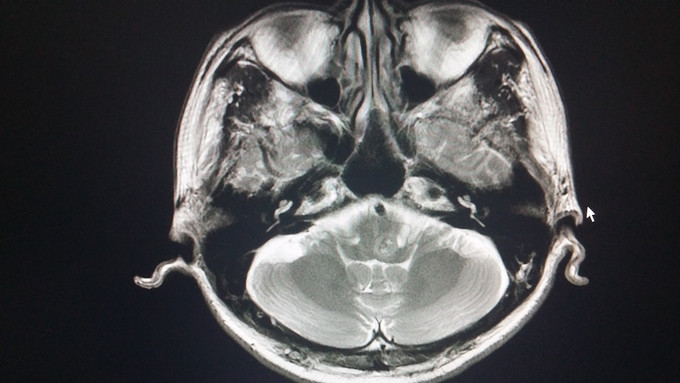

1、患者 男 67岁 体检发现颅内占位病变2月,右侧肢体麻木、头晕10天;既往有高血压病史 2、患者2月前体检行头颅CT检查发现右侧脑膜留,未做特殊处理,10天前无明显诱因出现右侧肢体麻木,头晕,饮水呛咳,口水及吃饭难于下咽,到当地医院就诊查头颅MRI:右侧蝶骨脊脑膜瘤可能,延髓偏左侧出血,海绵状血管瘤可能。

3、神清,伸舌居中,咽反射双侧消失;四肢肌力5级,右侧肢体感觉减退 4、头颅MRI:右侧蝶骨脊脑膜瘤可能,延髓偏左侧出血,海绵状血管瘤可能